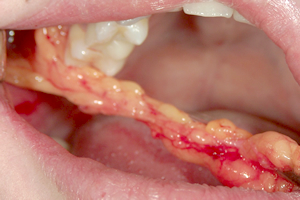

写真で見る「バッカルファットを除去する様子」

① 粘膜切開

② 粘膜剥離

切開はお口の中の頬の粘膜に、

左右1cmの小さな切開をおこないます。

軟膜切開に続いて、下顎骨筋突起を目指して、ペアンまたは、コッヘルを用いて、鈍的な剥離をおこないます。曲剥離剪刃を使用することもあります。

バッカルファットパット直下に至ると、卵黄色の薄い膜に包まれたバッカルファットを目視できます。直視下において、除去すべき脂肪を一塊に除去します。